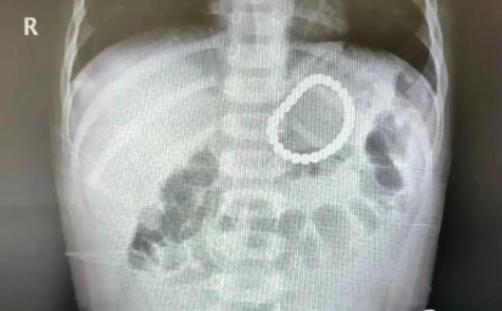

2岁幼童误吞28颗磁力珠 CT照片曝光实在是太吓人了

巴克球又称磁力珠,是一款备受欢迎的“网红”玩具,被很多家长认其有益于“开发大脑”、“拓展思维”和“提升动手能力”。

但对婴幼儿来说,这款玩具却暗藏着一定的危险。